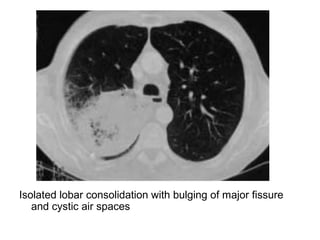

Isolated lobar consolidation with bulging of major fissure

and cystic air spaces